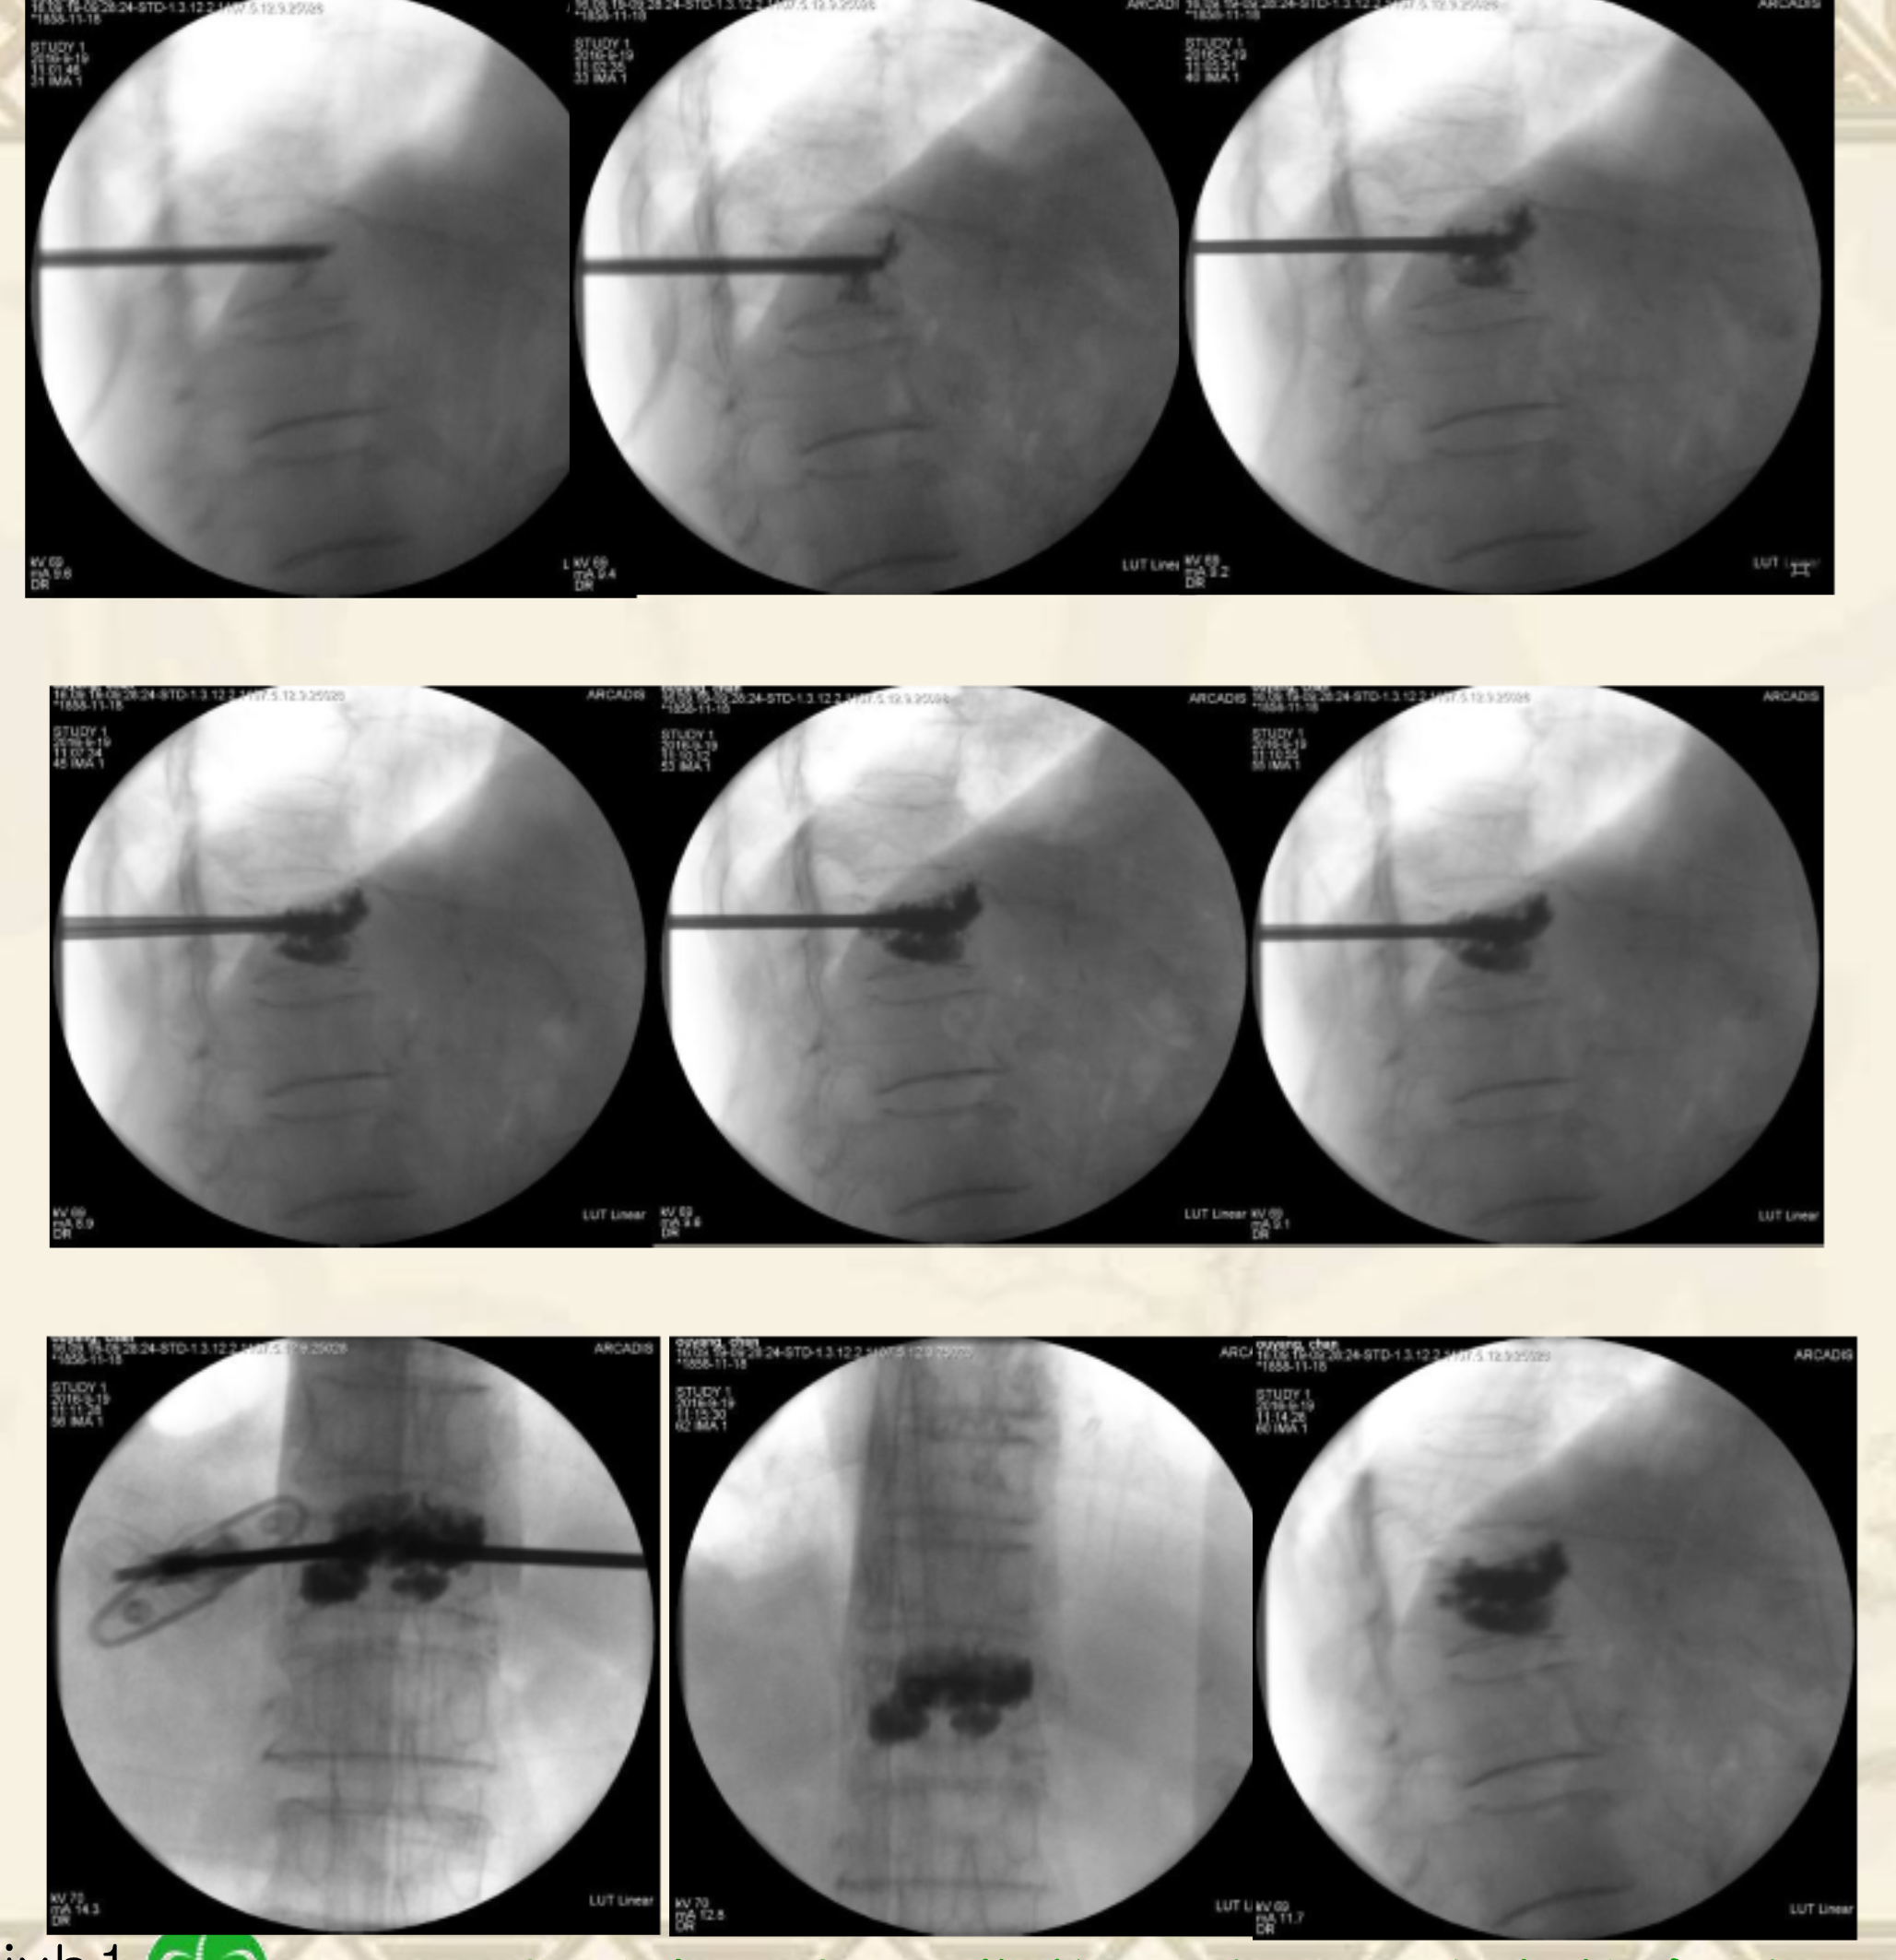

术中透视图

透视引导下,经椎弓根入路或根旁

靶向骨折区置管